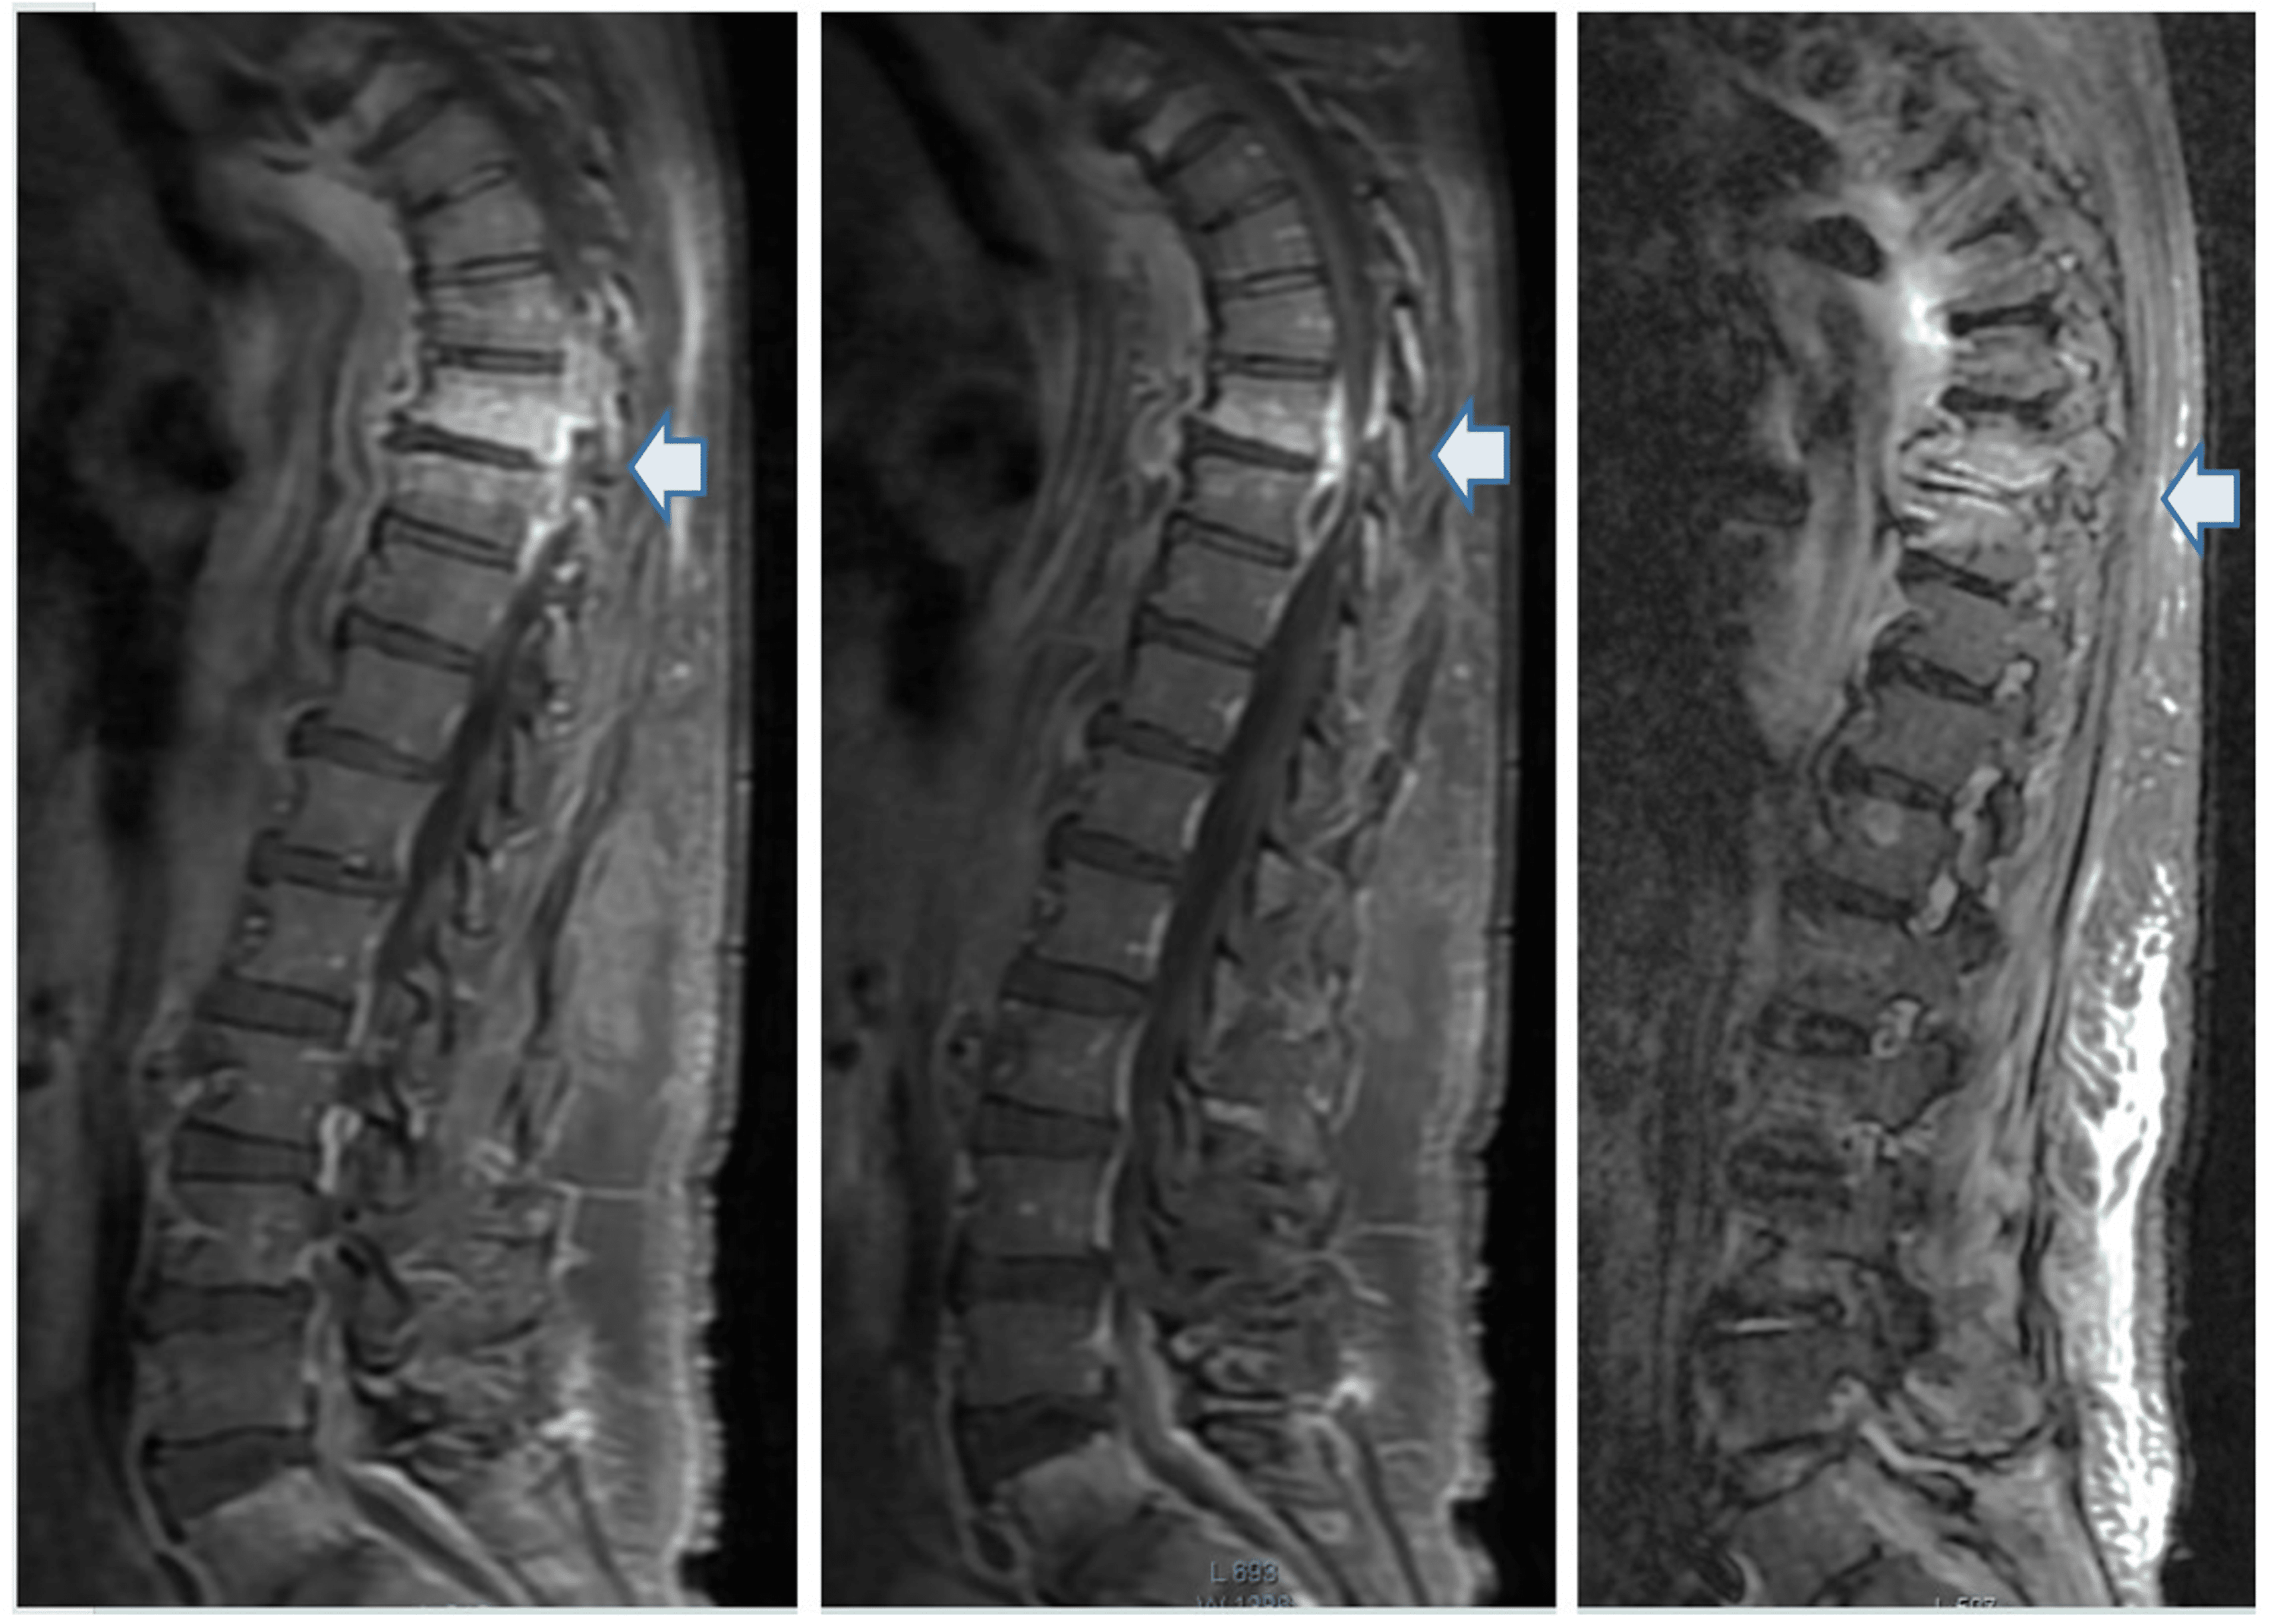

From www.researchgate.net

Sequential MRI findings in a 44yearold male with Pott’s spine. a... Download Scientific Diagram Pott's Disease Curable spinal tuberculosis (tb), also known as pott disease, is a form of tb that develops in your spine. the most common type is spinal tuberculosis. This happens when the mycobacterium infection spreads into your. can pott’s disease be cured? A cure isn’t possible in all situations,. despite questionable efficacy, prolonged recumbence and the use of frames,. Pott's Disease Curable.